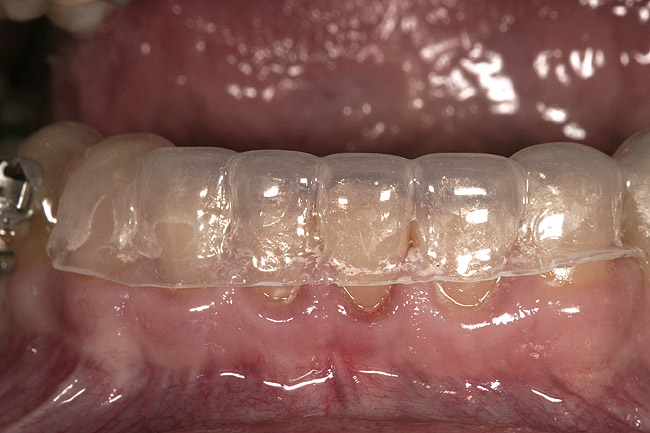

Figure 14  A 1.5-mm clear matrix is made from a diagnostic wax-up and tried in.

Figure 14

Figure 15  The teeth have been etched, the adhesive has been placed, and the matrix seated with composite.

Figure 15